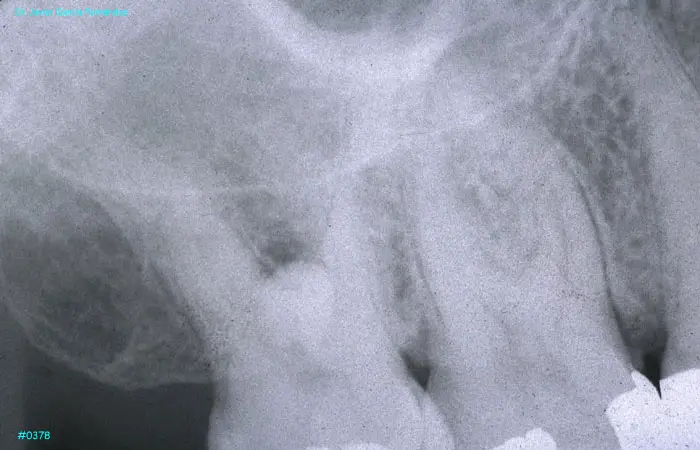

imagen 429